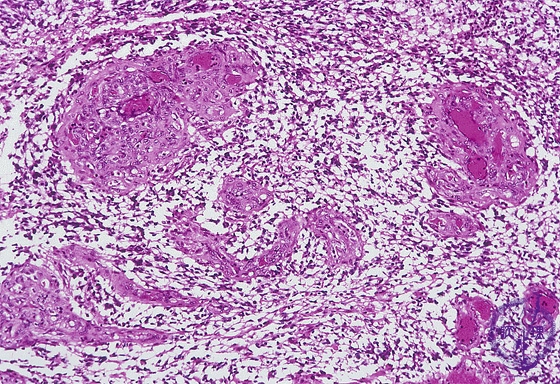

- ★(8)Glioma(Glioblastoma)

Microscopic findings (H.E. middle magnification): There were increased number of vessels with anintravascular proliferation of endothelial cells and thickening of the vascular wall (arrows). Sometimes, several vascular lumina were detected in a single vessel, also termed ‘glomeruloid structure’.